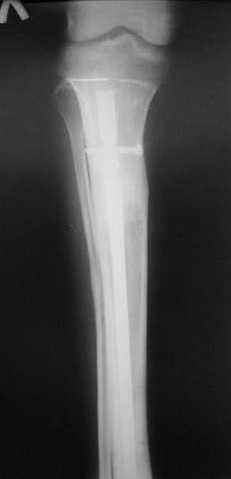

Пациент 19 лет, производственная травма, придавлен тяжелой плитой. Политравма (ISS 21).

1 - рентгенограмма (прошу прощения за качество) при поступлении;

Произведено ПХО, acute shortening (5 см), фиксация стержневым аппаратом Hoffman.